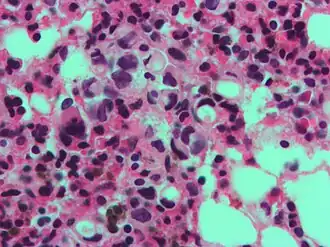

The name of the cell comes from its appearance; signet ring cells resemble signet rings. They contain a large amount of mucin, which pushes the nucleus to the cell periphery. The pool of mucin in a signet ring cell mimics the appearance of a finger hole and the nucleus mimics the appearance of the face of the ring in profile.

Gastric signet ring cell carcinoma. H&E stain. -

High magnification micrograph showing signet ring cells, with clear cytoplasm, in metastatic breast carcinoma. H&E stain. -